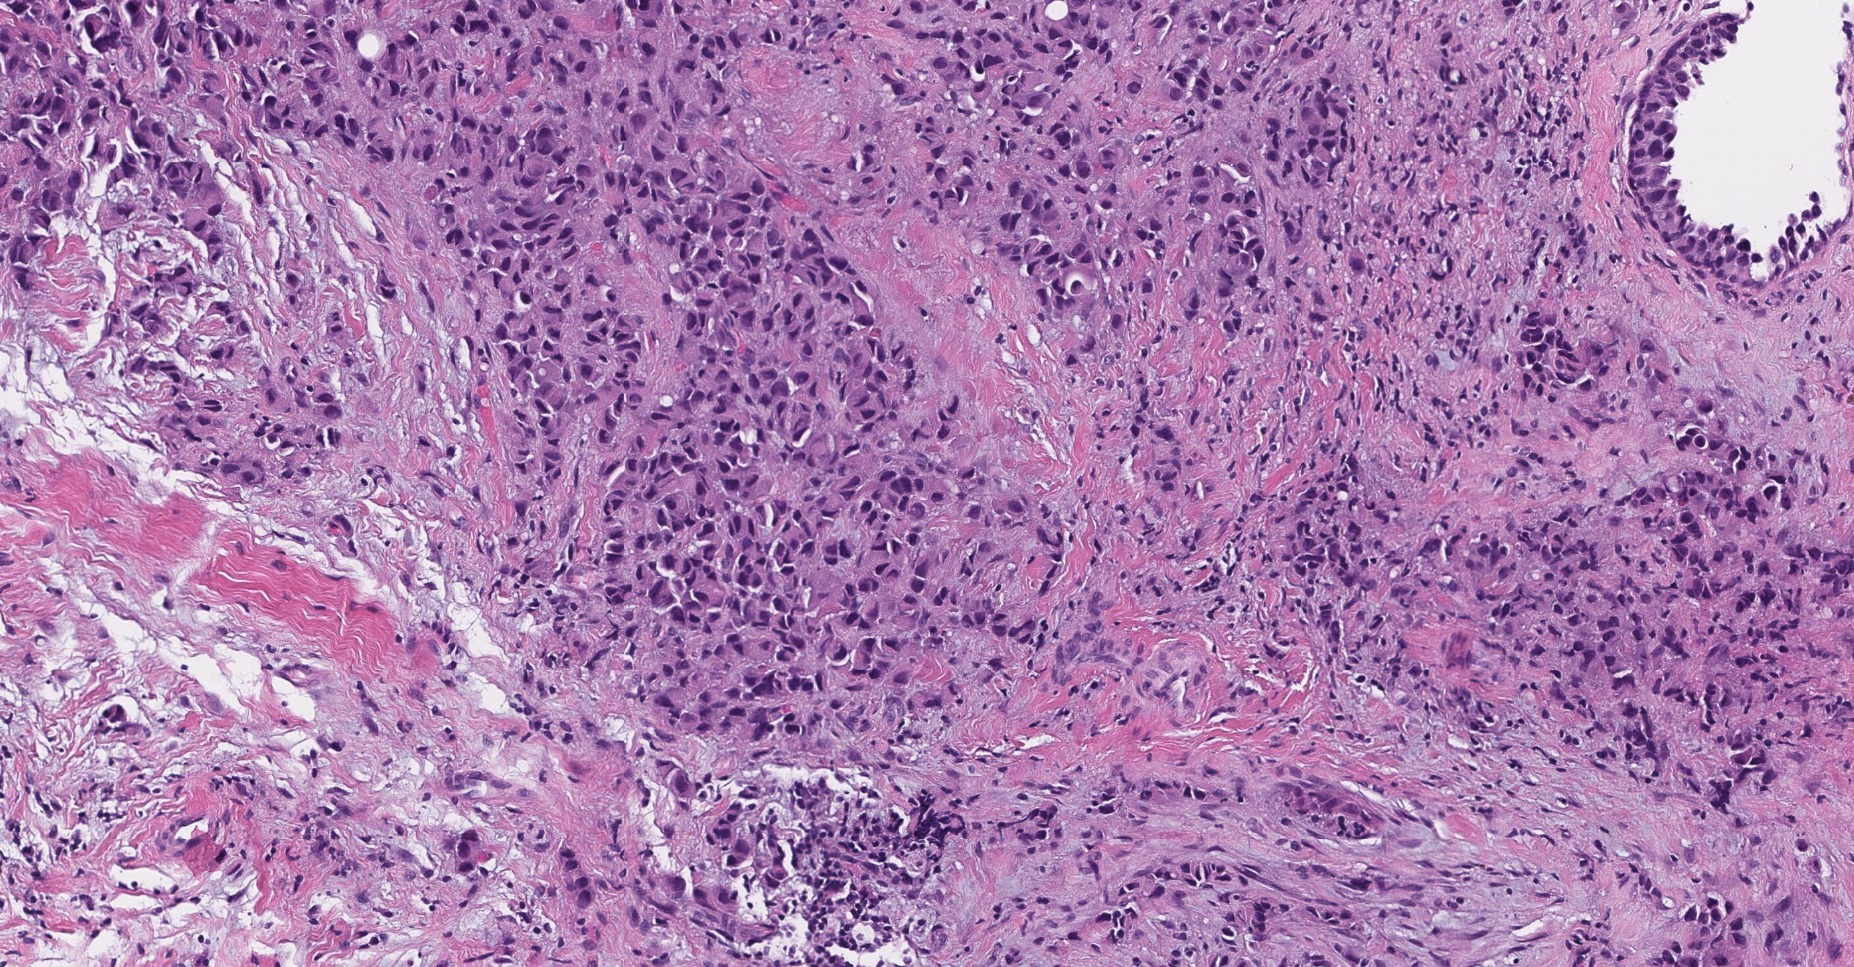

We process images of all kinds. As for medical imaging both structural and functional modalities like MRI, CT, PET, UH and X-ray are supported. Microscopy imaging for laboratory purposes offered in our portfolio include histopathology (H&E, IHC), cytology (e.g. pap smear), blood smear, cell culture and fertility/IVF. Regarding research we create solutions for brightfield and fluorescent microscopy, high-content screening, pharmaceutical testing, bacteria colony counting etc.

Handling large amounts of imaging data is carefully performed by developing software tools that smoothly fit into the workflow to accelerate scientific progress, discovery or diagnosis. Applying cutting-edge AI-driven approaches to process data we offer reliable and accurate quantitative analysis from raw input to conclusions whether for detection, classification, segmentation or tracking. We help the experts find tumours, anomalies, cellular response and insight with a personalized and supportive solution.

We develop state-of-the-art AI solutions for the automatic segmentation (e.g. tissue region, single cell), object detection (e.g. target cell, bacteria), classification (e.g. healthy vs malignant), tracking (e.g. movement) and progress monitoring (e.g. cell growth, confluence) of images.